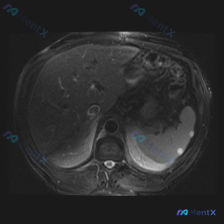

整理了一份很有意思的腹部影像病例,从单一病灶到全局判断,中间的思维路径值得复盘: --- 影像基础信息 - 序列:腹部MRI T2加权成像(T2WI)轴位 - 背景脂肪信号未抑制,为标准T2WI 关键影像表现 1. 脾脏病灶: - 位置:脾脏边缘(外侧) - 数量:2个类圆形结节 - 信号:T2WI...